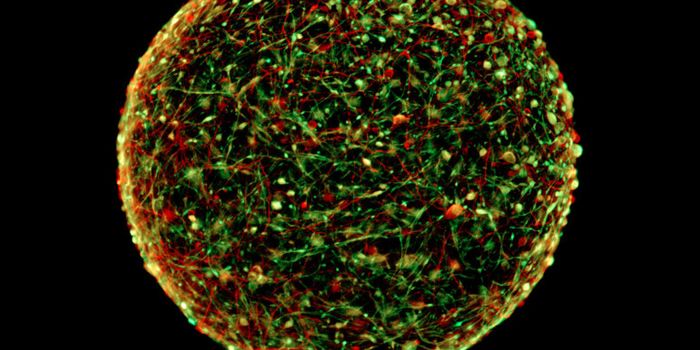

MAR 08, 2016ImmunologyScientists have grown tiny, barely visible “mini-brains.” These balls of neurons and other human cells mimic ...